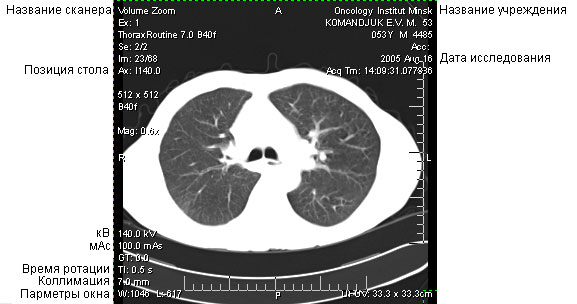

С целью оценки доз облучения пациентов при КТ-исследованиях дозиметрию производят с использованием клинических протоколов КТ-исследований, т.е. применяемых при сканировании пациентов.

Основными параметрами КТ-исследования, определяющими дозу облучения,

являются:

- технология сканирования (последовательная, спиральная, многосрезовая) и конфигурация

детектора, рентгеновского излучения (для многосрезовых сканеров),

- напряжение в рентгеновской трубке (кВ),

- сила тока в рентгеновской трубке (мА),

- время ротации, т. е. полного (360°) оборота вокруг пациента,

- коллимация среза,

- сдвиг стола за ротацию,

- длина области сканирования,

- количество сканирований (например, до и после в/в введения контрастного вещества

или нескольких областей исследования).

Измерение доз облучения производится при параметрах протоколов КТ-исследований, собранных на Первом этапе. В процессе дозиметрии необходимо строго придерживаться этих параметров, в результате чего будут установлены дозы облучения при рутинно используемых в конкретном учреждении КТ-исследованиях. По результатам измерений заполняется протокол дозиметрии.

Пример заполнения протокола

КТ-дозиметрии